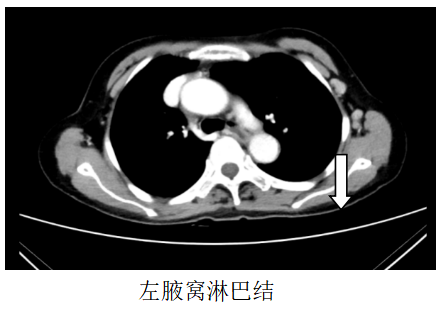

胸部CT:1、左锁骨区、左腋窝多发肿大淋巴结,考虑转移,建议随访,全腹CT:考虑食管胃交界癌累及胃周脂肪并腹腔腹膜后淋巴结多发转移(CT分期约T4aN3)。

图1.2019.7.5影像(基线评估)

诊断:食管胃交界腺癌腹腔、腹膜后、左腋窝、左锁骨区淋巴结转移脑转移(cT4aN3M1,IV期,HER2扩增,MSS,PD-L1-)